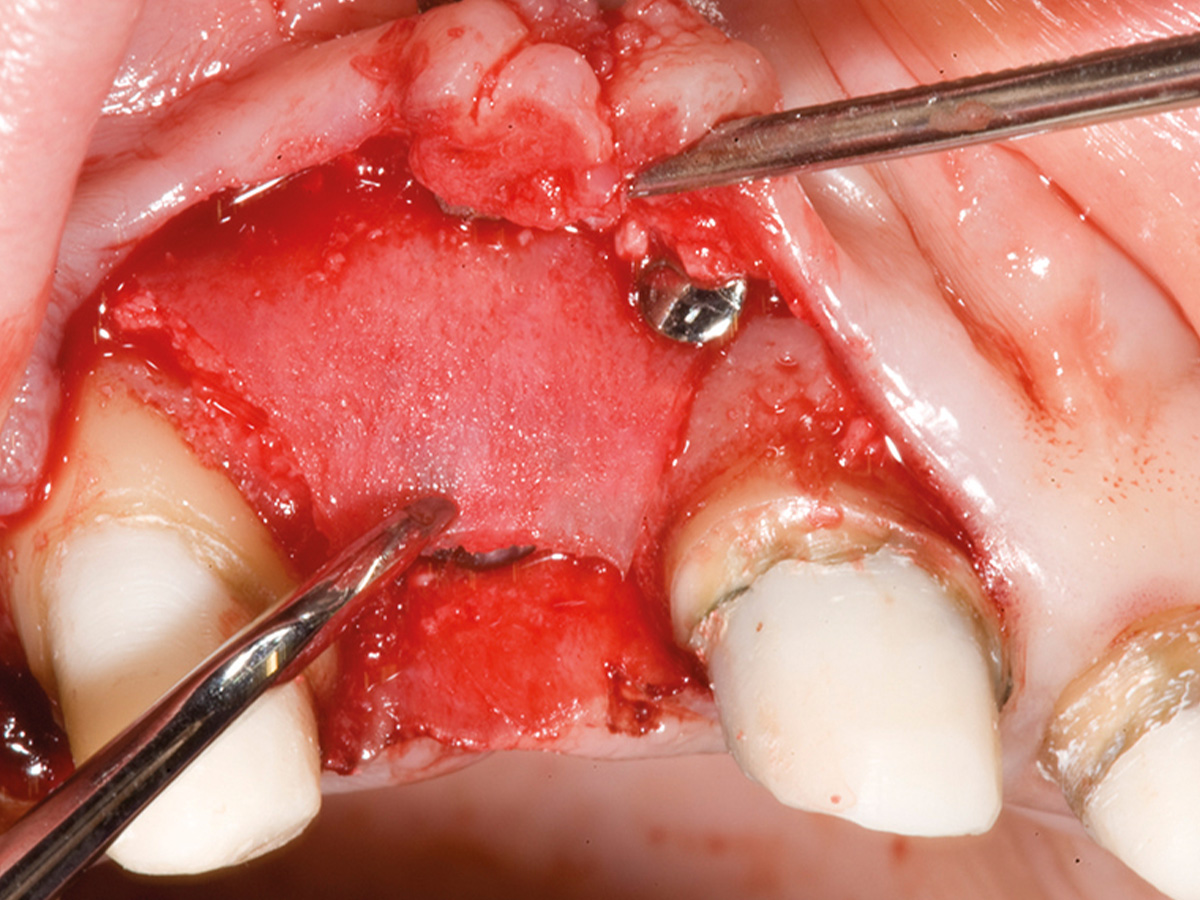

Abbildung 4

Intraoperative Situation mit koronaler Knochenbrücke und extraalveolär imponierendem Implantat (Biomet 3,2 x 13).